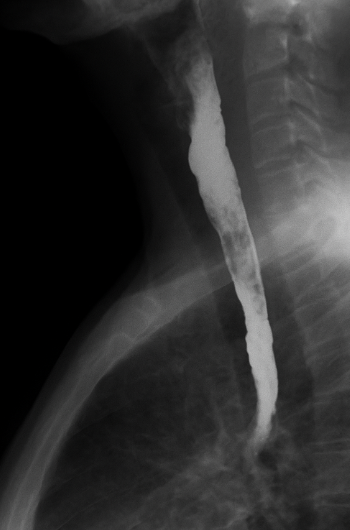

Esophagogram: Esophageal deviation to the right in its upper and middle third. No contrast leakage sites observed (Figure 4).

Esophagogram. Esophageal deviation to the right in its upper and middle third.